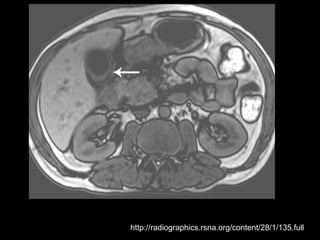

Colecistite Xantogranulomatosa

Na TC:

Os cálculos biliares e o espessamento irregular

semelhante a uma massa da parede da VB são as

anormalidades mais comuns.

Vários estudos relataram que os nódulos

hipoatenuantes intramurais vistos na TC

representam uma lesão xantogranulomatosa, um

abscesso ou a combinação de ambos;

Realce da superfície luminal(70%) correspondia à

presença de uma camada epitelial.

Colecistite Xantogranulomatosa Na TC: Os cálculos biliares e o espessamento irregular semelhante a uma massa da parede da VB são as anormalidades mais comuns. Vários estudos relataram que os nódulos hipoatenuantes intramurais vistos na TC representam uma lesão xantogranulomatosa, um abscesso ou a combinação de ambos; Realce da superfície luminal(70%) correspondia à presença de uma camada epitelial.